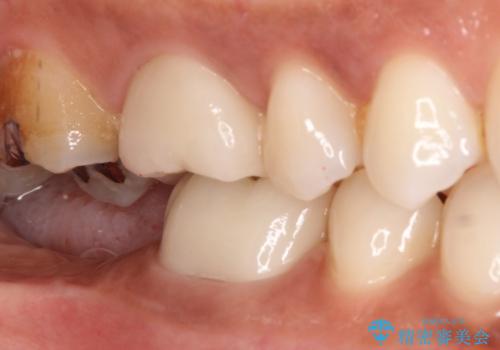

根管治療を行なったのちオールセラミッククラウンにて修復補綴を行いました。

根管治療歯は破折を防止するために速やかに被せ物の治療を提案いたします。